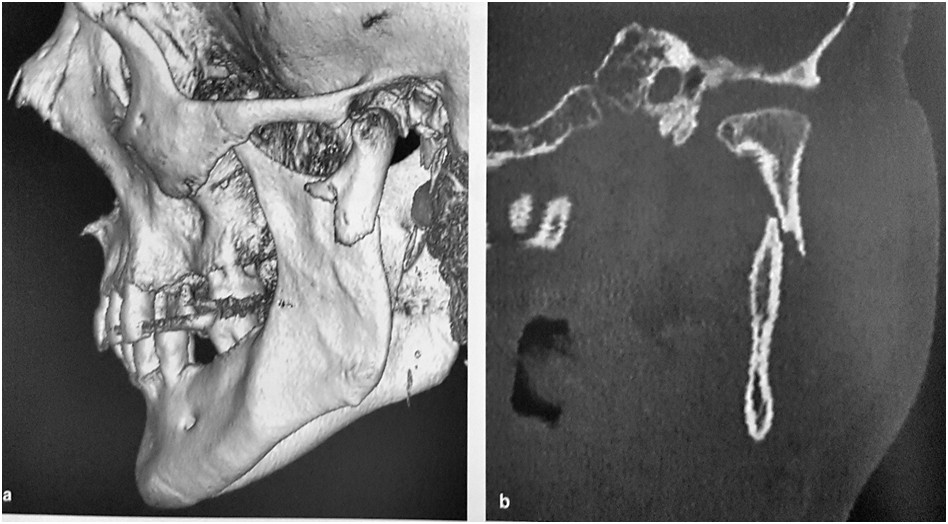

Rycina przedstawia badanie tomografii komputerowej w zakresie twarzowej części czaszki. Wskaż właściwe rozpoznanie:

Na rycinie przedstawiono jeden z uniwersalnych dostępów chirurgicznych do wyrostka kłykciowego. Jest to dostęp: